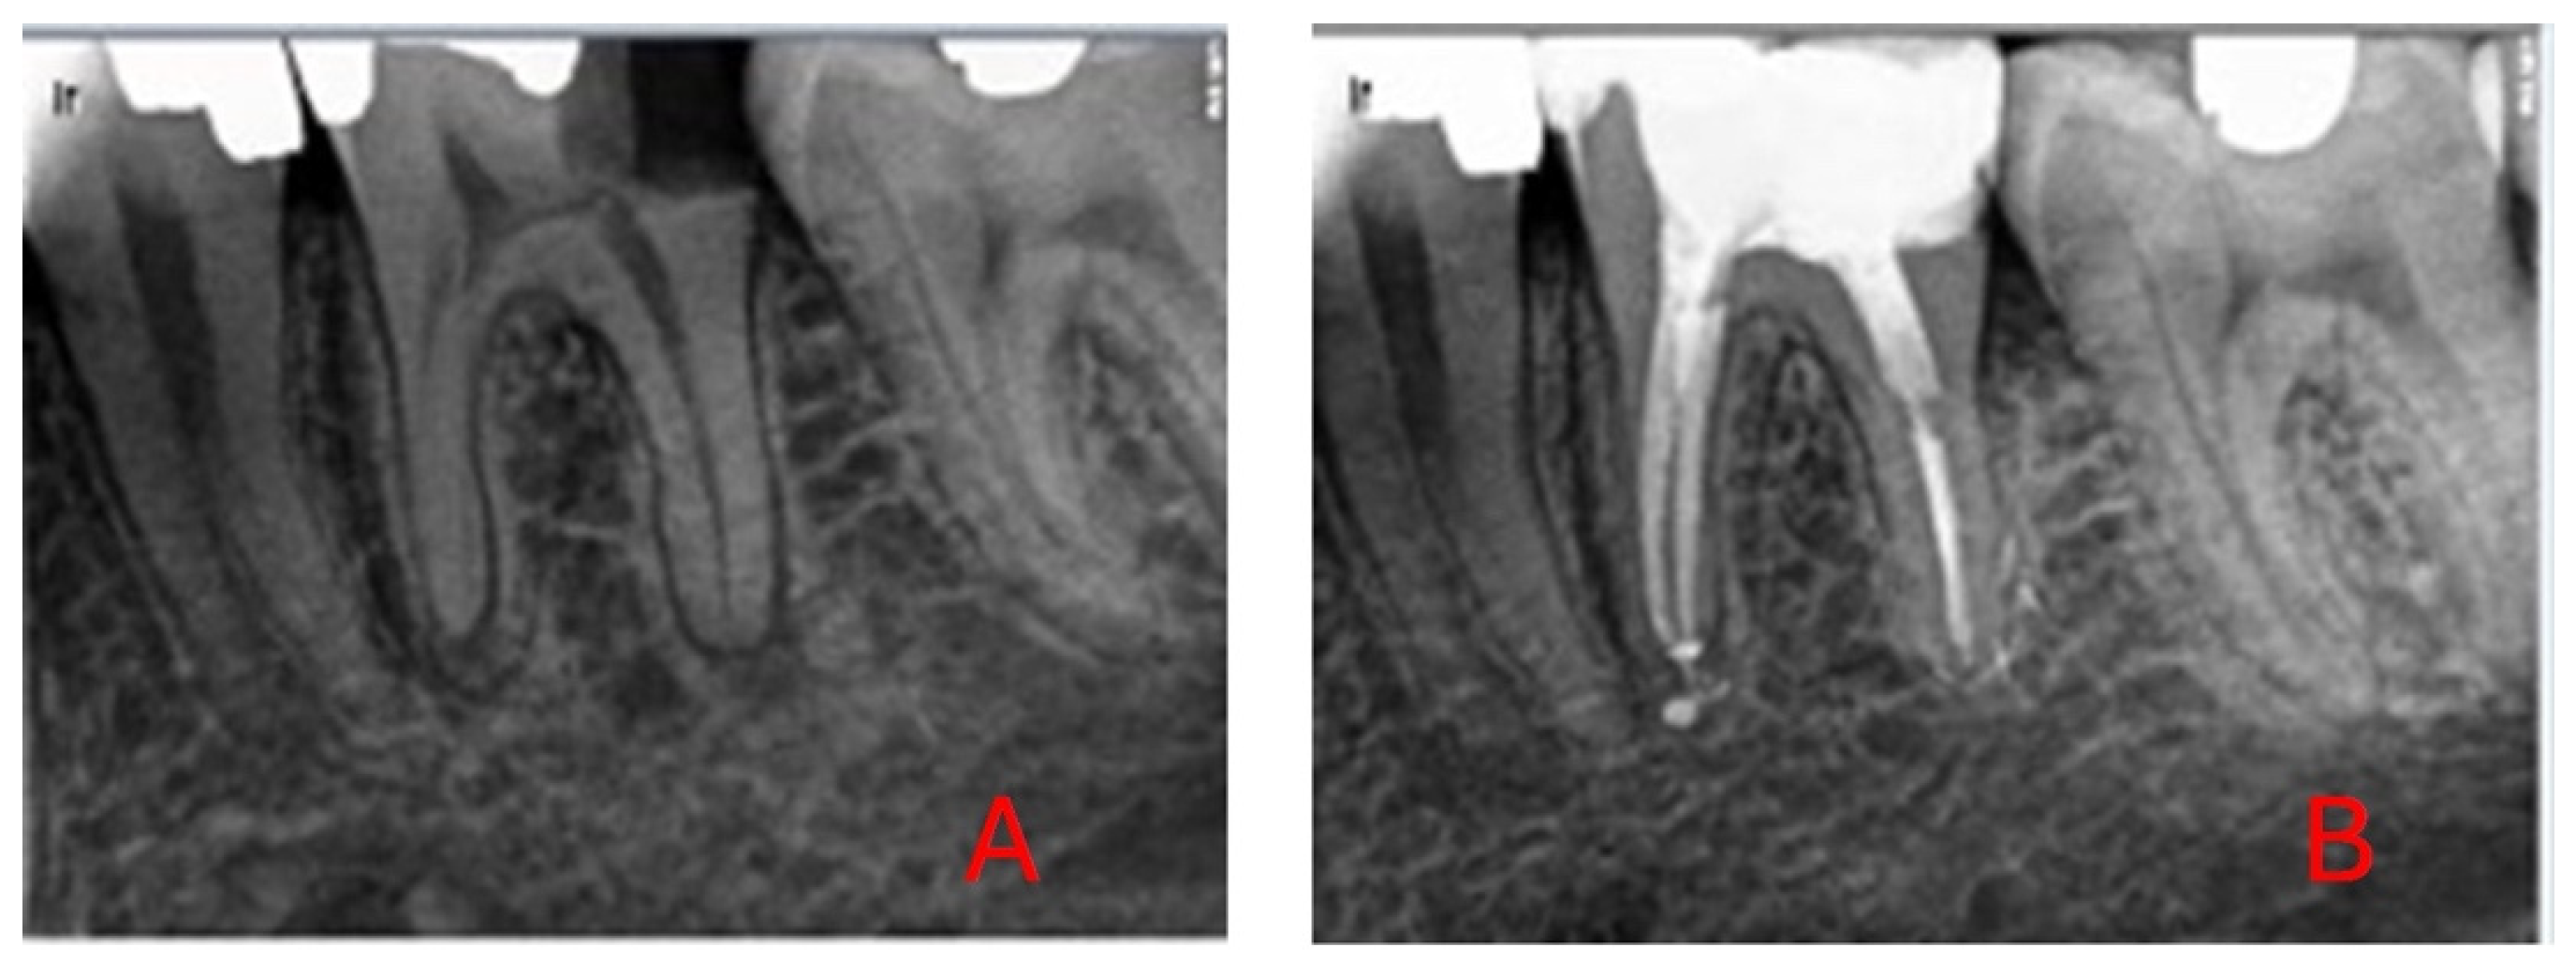

3.1. Sample Selection

3.2. Intervention Procedure